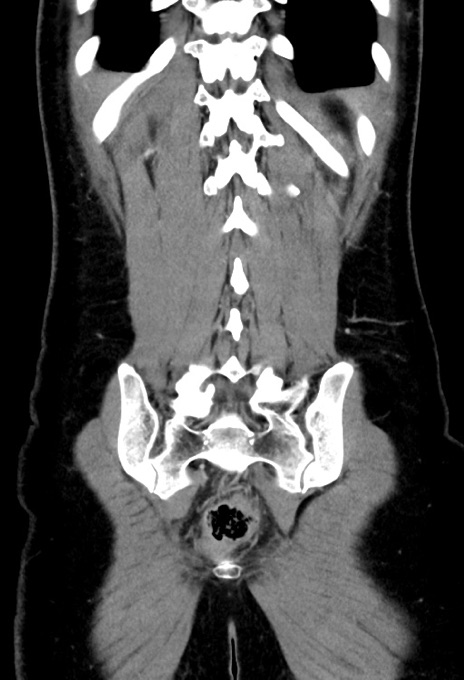

症例17(冠状断像)

【症例】20歳代女性

【主訴】嘔吐、下腹部痛

【現病歴】昨日夕食後に嘔吐し下腹部痛が出現。本日になっても嘔吐持続し改善しないため来院。

【身体所見】意識清明、BT 37.2℃、BP 108/67mmHg、腹部:平坦、やや硬、下腹部正中から右にかけて圧痛あり、反跳痛軽度あり、tapping pain(+)。

【データ】WBC 13600、CRP 14.94